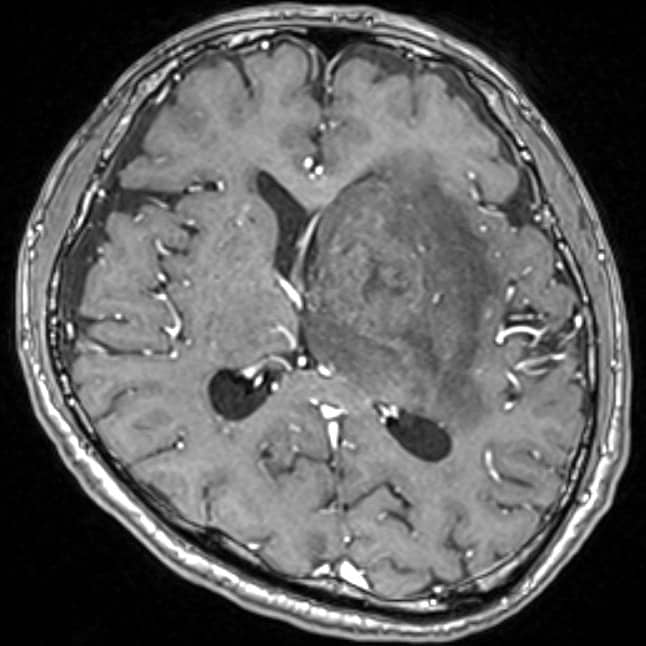

認知機能低下、行動異常、右不全片麻痺の進行を認め、頭蓋内の精査目的に頭部MRIが施行された。左大脳基底核に腫瘍性病変および腫瘍周囲浮腫の所見を認めた。同病変は、造影T1強調像画像では極めて淡い軽度の造影効果を示し、拡散強調画像では軽度の高信号、ADC画像では低信号を示した。診断確定のため生検手術を行った。生検手術1週間後に頭部MRIを施行すると、術前に施行した頭部MRIとは所見が変化し、左大脳基底核の病変は造影T1強調画像では明瞭な造影効果を認め、拡散強調画像でも高信号の増強、ADC画像では低信号を示した。病理組織学的診断は中枢神経系原発悪性リンパ腫であった。そのためR-MPV療法(リツキシマブ、メトトレキサート、プロカルバジン、ビンクリスチン)を施行した。R-MPV療法の経過中の頭部MRIでは、左大脳基底核の病変は縮小傾向を認め、それに伴い初診時に認めていた認知機能低下、行動異常、右不全片麻痺は改善傾向にあり、良好に経過している。